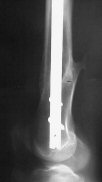

I presented a series of ~25 such cases at EuroTrauma'2004. Many cases were discussed here. I attach am example. Look also recent cases at http://www.hwbf.org/hwb/conf/alex58/scfx.htm,

http://www.hwbf.org/hwb/conf/alex63/alex63.htm

THX, initial images are

1,

2.

At that moment we had in stock only the 10 mm solid nails so of course there was no idea about early weight bearing. But it was quite enough for early knee ROM excersises (see attached). Two locking screws through the distal block provided that.